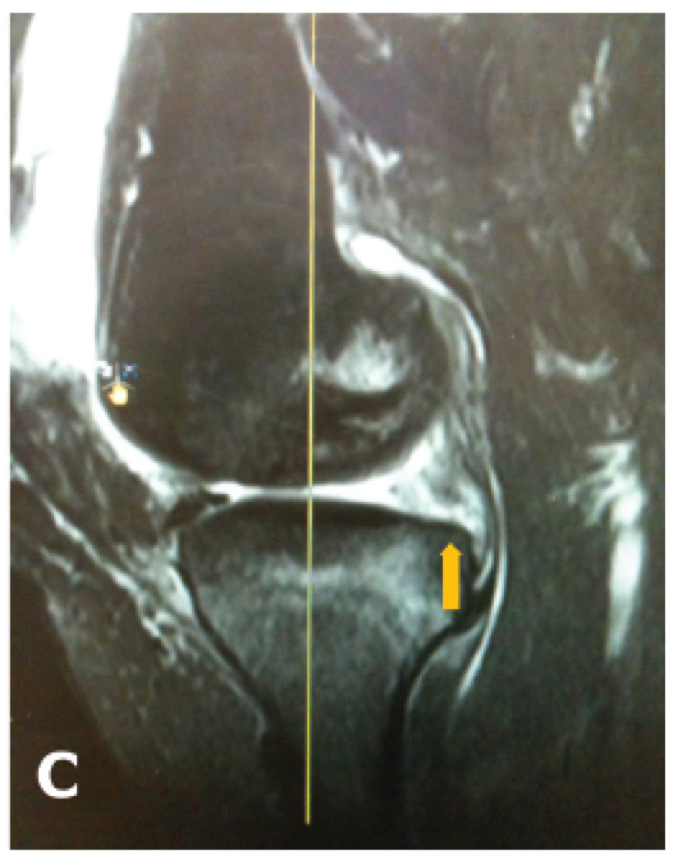

MRI

Findings

- meniscal extrusion

- meniscal ghost sign on sagittal (missing meniscus)